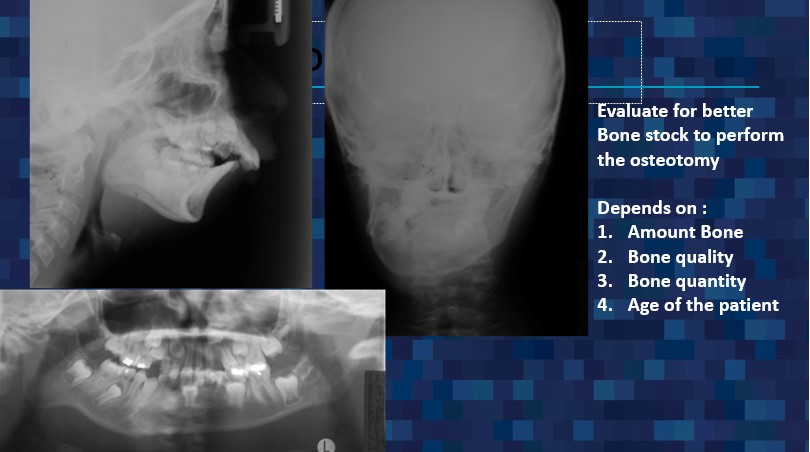

For over 30 years, Dr. Guerrero has made it his mission to improve the lives of his patients through specialized surgical care that restores function and comfort. Dr. Guerrero’s work embodies precision, compassion, and a dedication to patient well-being. Corrective jaw surgery is one of the advanced services offered, designed to address functional issues and enhance the quality of life for those who need realignment and reconstruction.